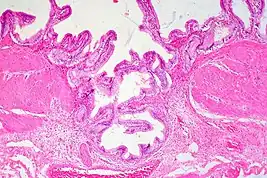

Rokitansky-Aschoff Sinus, Gallbladder Adenomyomatosis

Adenomyomatosis is frequently associated with gallstones and is often diagnosed incidentally, either from a cholecystectomy specimen or autopsy.[4][5][6] No serologic test exists to specify adenomyomatosis and laboratory studies are often normal. Co-existing diseases like cholecystitis may result in abnormal test results, such as elevated levels of white blood cells (leukocytosis), liver enzymes (transaminitis), or bilirubin (hyperbilirubinemia).[5]

Ultrasound is the preferred initial diagnostic choice for suspected gallbladder disease. Several distinct features of adenomyomatosis are discernable using ultrasound, making it a reliable modality for diagnosis.[4][5][6] The most characteristic features seen on ultrasound are the Rokitansky-Aschoff sinuses, which present either as echogenic foci when filled with biliary sludge/gallstones or anechogenic foci when filled with normal bile.[4][5][6] Other key features that may be seen include wall thickening and ring-down artifacts known as "comet tails" (produced by reverberations of sound between the sinuses).[4][5][6] Ultrasound can also distinguish between diffuse, segmental, and localized variants of adenomyomatosis based on morphology.[5][6]

In some cases, gallbladder wall thickening may be seen on ultrasound but is poorly defined and lacking specificity, particularly if the characteristic Rokitansky-Aschoff sinuses are not visualized. This can make it difficult to distinguish adenomyomatosis from other conditions that result in gallbladder wall thickening such as gallbladder cancer.[4][5][6] In these cases, MRI can prove helpful in providing the resolution needed for diagnosis. Especially effective is the T2-weighted MRI at visualizing the pathognomonic Rokitansky-Aschoff sinuses, which appear as round-shaped hyperintense cystic spaces that align in a curvilinear fashion along the gallbladder wall in a pattern described as the ”pearl necklace sign”.[4][5][6]